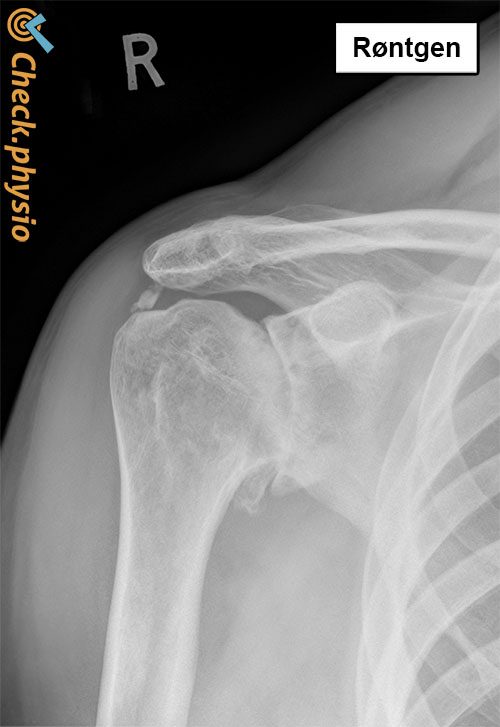

Etter en samtale med lege eller fysioterapeut om plagene, følger en klinisk undersøkelse. Her vurderes skulderens bevegelighet. Ved alvorlige eller uklare symptomer tas det røntgenbilde. Bildet viser innsnevring i leddspalten mellom skulderhodet og -skålen. Eventuell osteofyttdannelse er også synlig.

Artrose deles inn i fire nivåer. I verste fall er brusken helt borte. Ved artrose endrer leddet seg og det kan oppstå betennelse i slimhinnen rundt skulderleddet. Små benete utvekster dannes i kanten av beinet; disse kalles osteofytter.